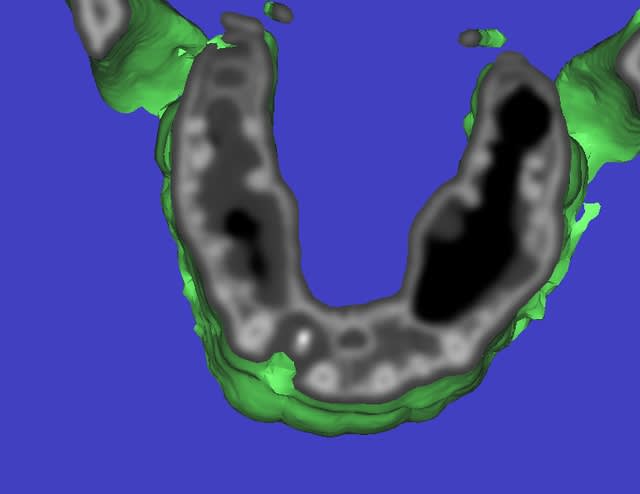

pano....youpie...scan...et là je crois qu'on décroche le ponpon...

t'as vu la taille du kyste??? il va jusqu'au sinus et se prolonge derrière la 11...la 12 ne tiens que par son ligament palatin...

pour D57...voussure vestibulaire...je sais pas trop s'il reste une corticale...ou si oui ultrafine...

le risque...perforation du sinus si la membrane kystique y adhère fortement...

je pensais tenter une sorte de ROG...en tapissant le fond (vers le sinus) avec une membrane collagène, et une autre vestibulaire au cas où il n'y ait plus d'os...

la question est plutôt...que mettre entre...

rien, des éponges hémostatiques, du biomat (lequel???biooss??) voir une membrane titane pour bien maintenir le volume???

Bon, preparation d'un provisoire, avulsion et nettoyage ultraminutieux, ça m'étonnerait bien qu'il n'y ait plus aucune corticale entre kyste et sinus, sinon ça va être chaud!

Puis ROG Biobank + membrane titane cloutée.